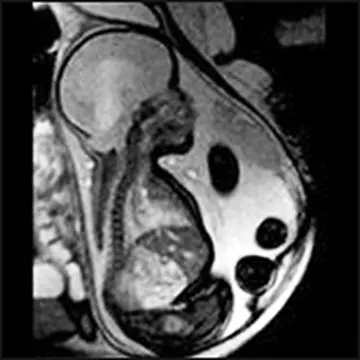

رادیولوژی - صفحه 3